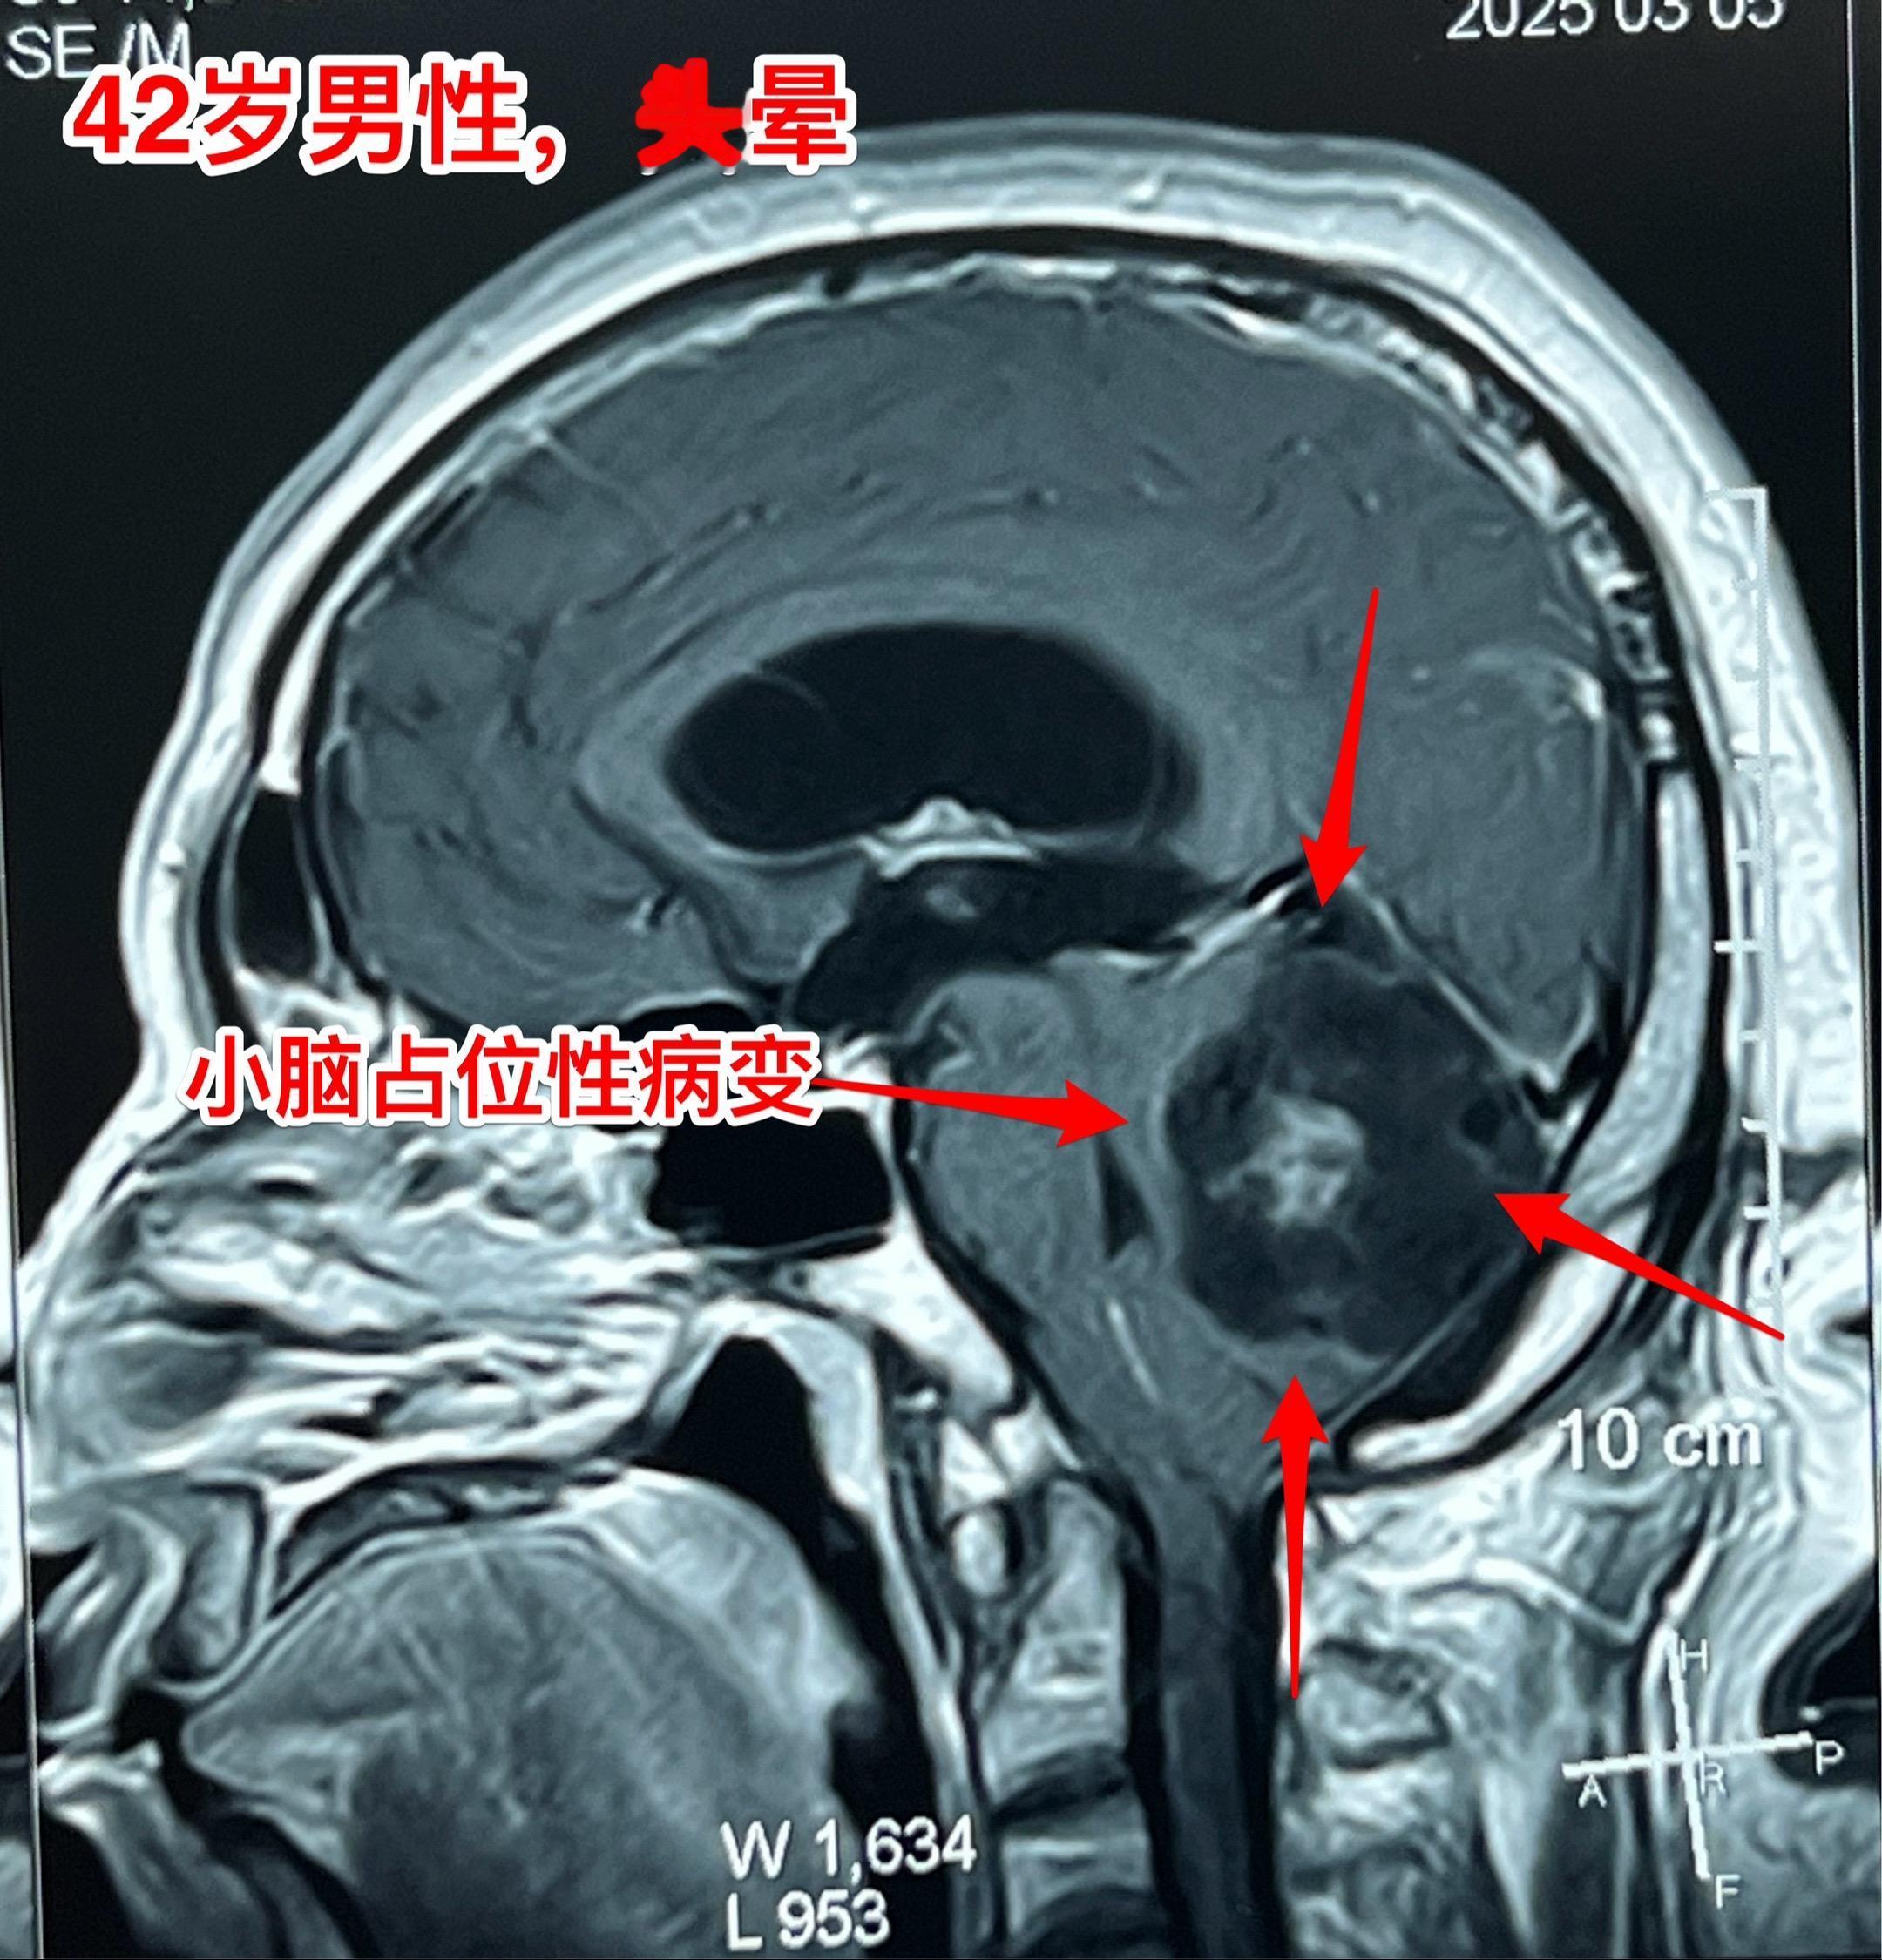

表皮样囊肿(胆脂瘤)并不是真正的肿瘤。这是先天性胚胎发育异常造成的疾病,脑部发育过程中神经管闭合时,一小部分外胚层细胞被关在脑子里面了。本来要发育成皮肤的细胞留在脑子里面,逐步增大,就形成了表皮样囊肿,也叫珍珠瘤,或者胆脂瘤。它不是真正的肿瘤,是表皮细胞脱落逐步增大形成了一个占位性病变。这个病也有恶变的,几率很小。 这个42岁的内蒙古男性,因头晕怀疑颈椎病,在锡林浩特作磁共振检查发现了小脑表面有个占位性病变,见图。DWI显示病灶是白色的,可以确诊为表皮样囊肿。 昨日作了手术